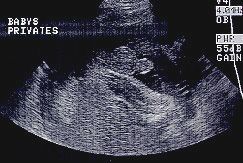

عکس جنین پسر در سونوگرافی هفته بیستم و هشتم بارداری

در این عکس در هفته بیست و هشتم بارداری ک سونوگرافی معمولی نیز دستگاه تناسلی جنین معلوم است. جنین شما به اندازه یک بادمجان است و 37.6 سانتی متر قد دارد. وزن نی نی شما حالا 1005 گرم است.